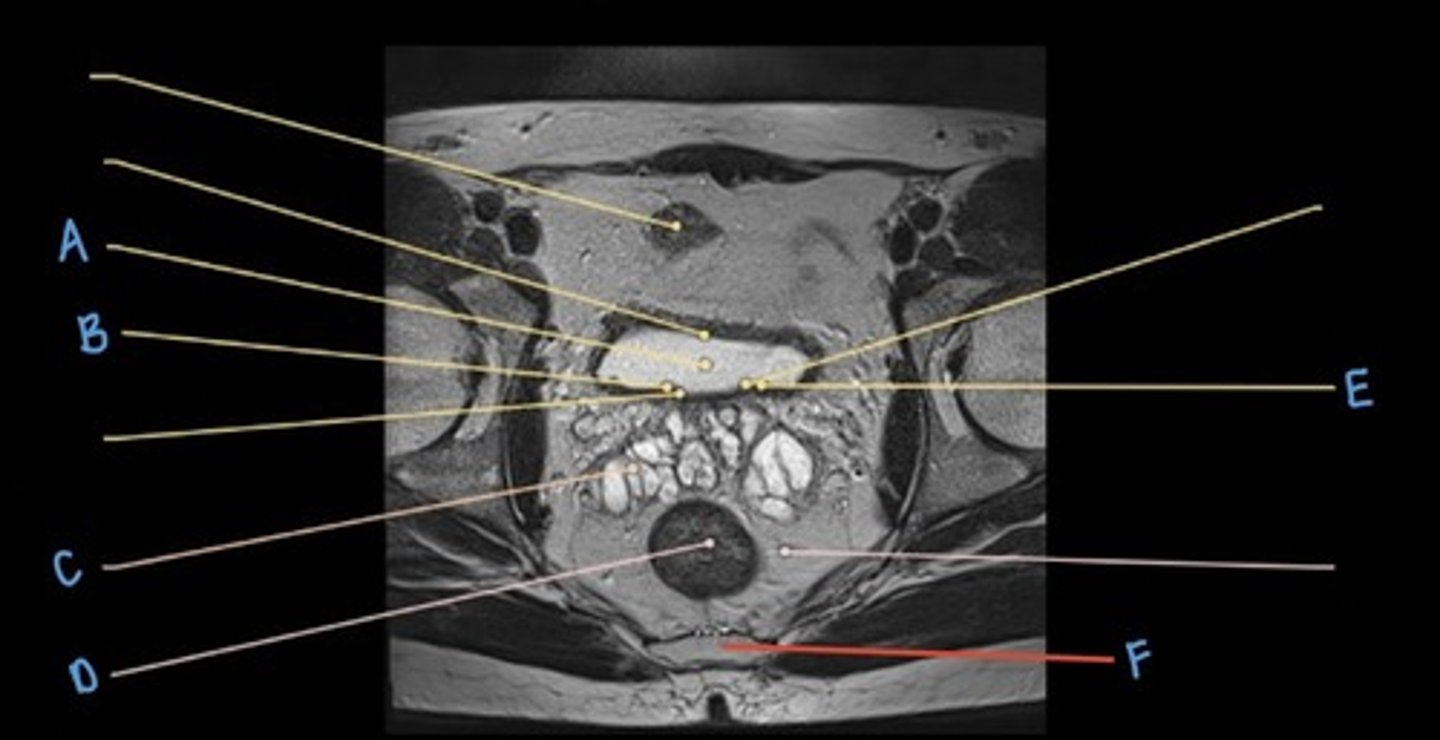

sigmoid colon

A

seminal vesicles

B

prostate

C

rectum

D

pubic symphysis

E

retro-pubic space

F

bladder

G